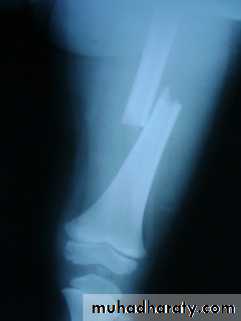

Arthroscopic repair used for peripheral lesionsInjuries of the tibia

Tibial plateau fractures:Direct blow or fall from height may cause fracture of one tibial condyle or both.

Fracture lateral condyle is the commonest named as bumper fracture

caused by a force that abducts the tibia upon femur while the foot is fixed on ground.Patient usually is an adult, the knee joint is swollen, bruises, there is diffuse tenderness and doughy feel of haemarthrosis.

ligaments injuries must be excluded.

Imaging : X-ray

: anteroposterior, lateral & oblique views.

CT -Scan may used to detect amount of depression and comminuation.Tibial plateau fracture

Treatment:

Undisplaced fractures

treated conservatively:Haemarthrosis aspiration and compression bandaging,

above knee cast for one monthsfollowed by functional brace and physiotherapy.

For displaced fracturestreatment is by open reduction and internal fixation with

plate and screws as it is an intra articular fracture.fixation of tibial plateau fracture